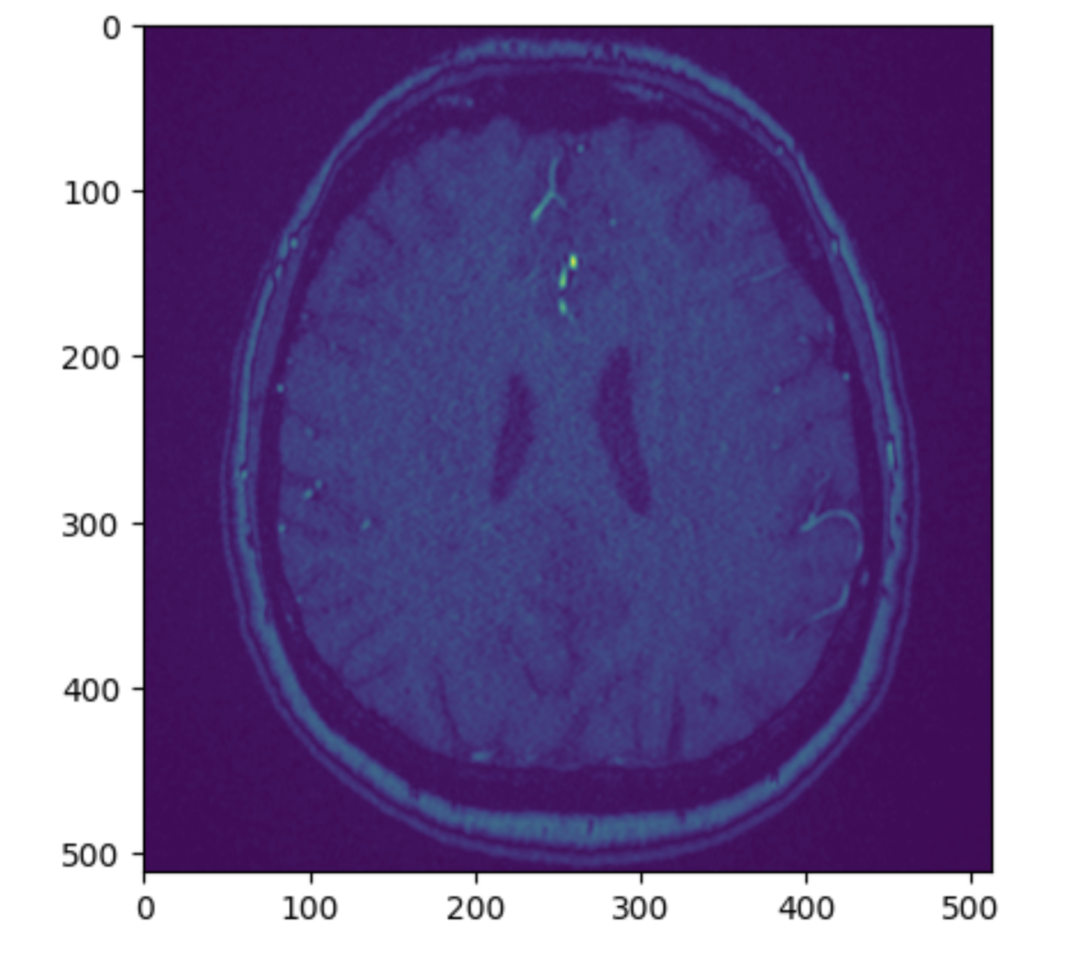

赛题任务:检测是否存在颅内动脉瘤,并精确定位其位置。

构建一个机器学习模型,利用多模态医学影像数据,检测是否存在颅内动脉瘤,并精确定位其位置。

包含了数千个由专家精心整理的脑部医学影像序列,这些影像来自多种不同的成像模式。每个序列都已被标注,指示在十三个可能的血管位置之一是否存在动脉瘤。